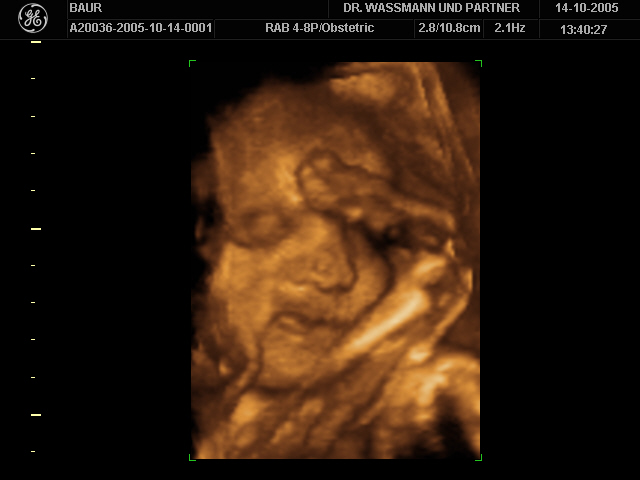

So, und jetzt noch ein 3D-Ultraschallbild unserer Kleinen von der 30. SSW. War gar nicht so einfach zu entscheiden welches ich euch zeige - sind doch alle so niedlich.

Susanne: Das "Bauchbild von innen" ist wirklich lieb. Ein süßes Mäuschen.

Da kann man wirklich stolz drauf sein! Nun sind wir aber gespannt auf das nächste Bauchbild!!